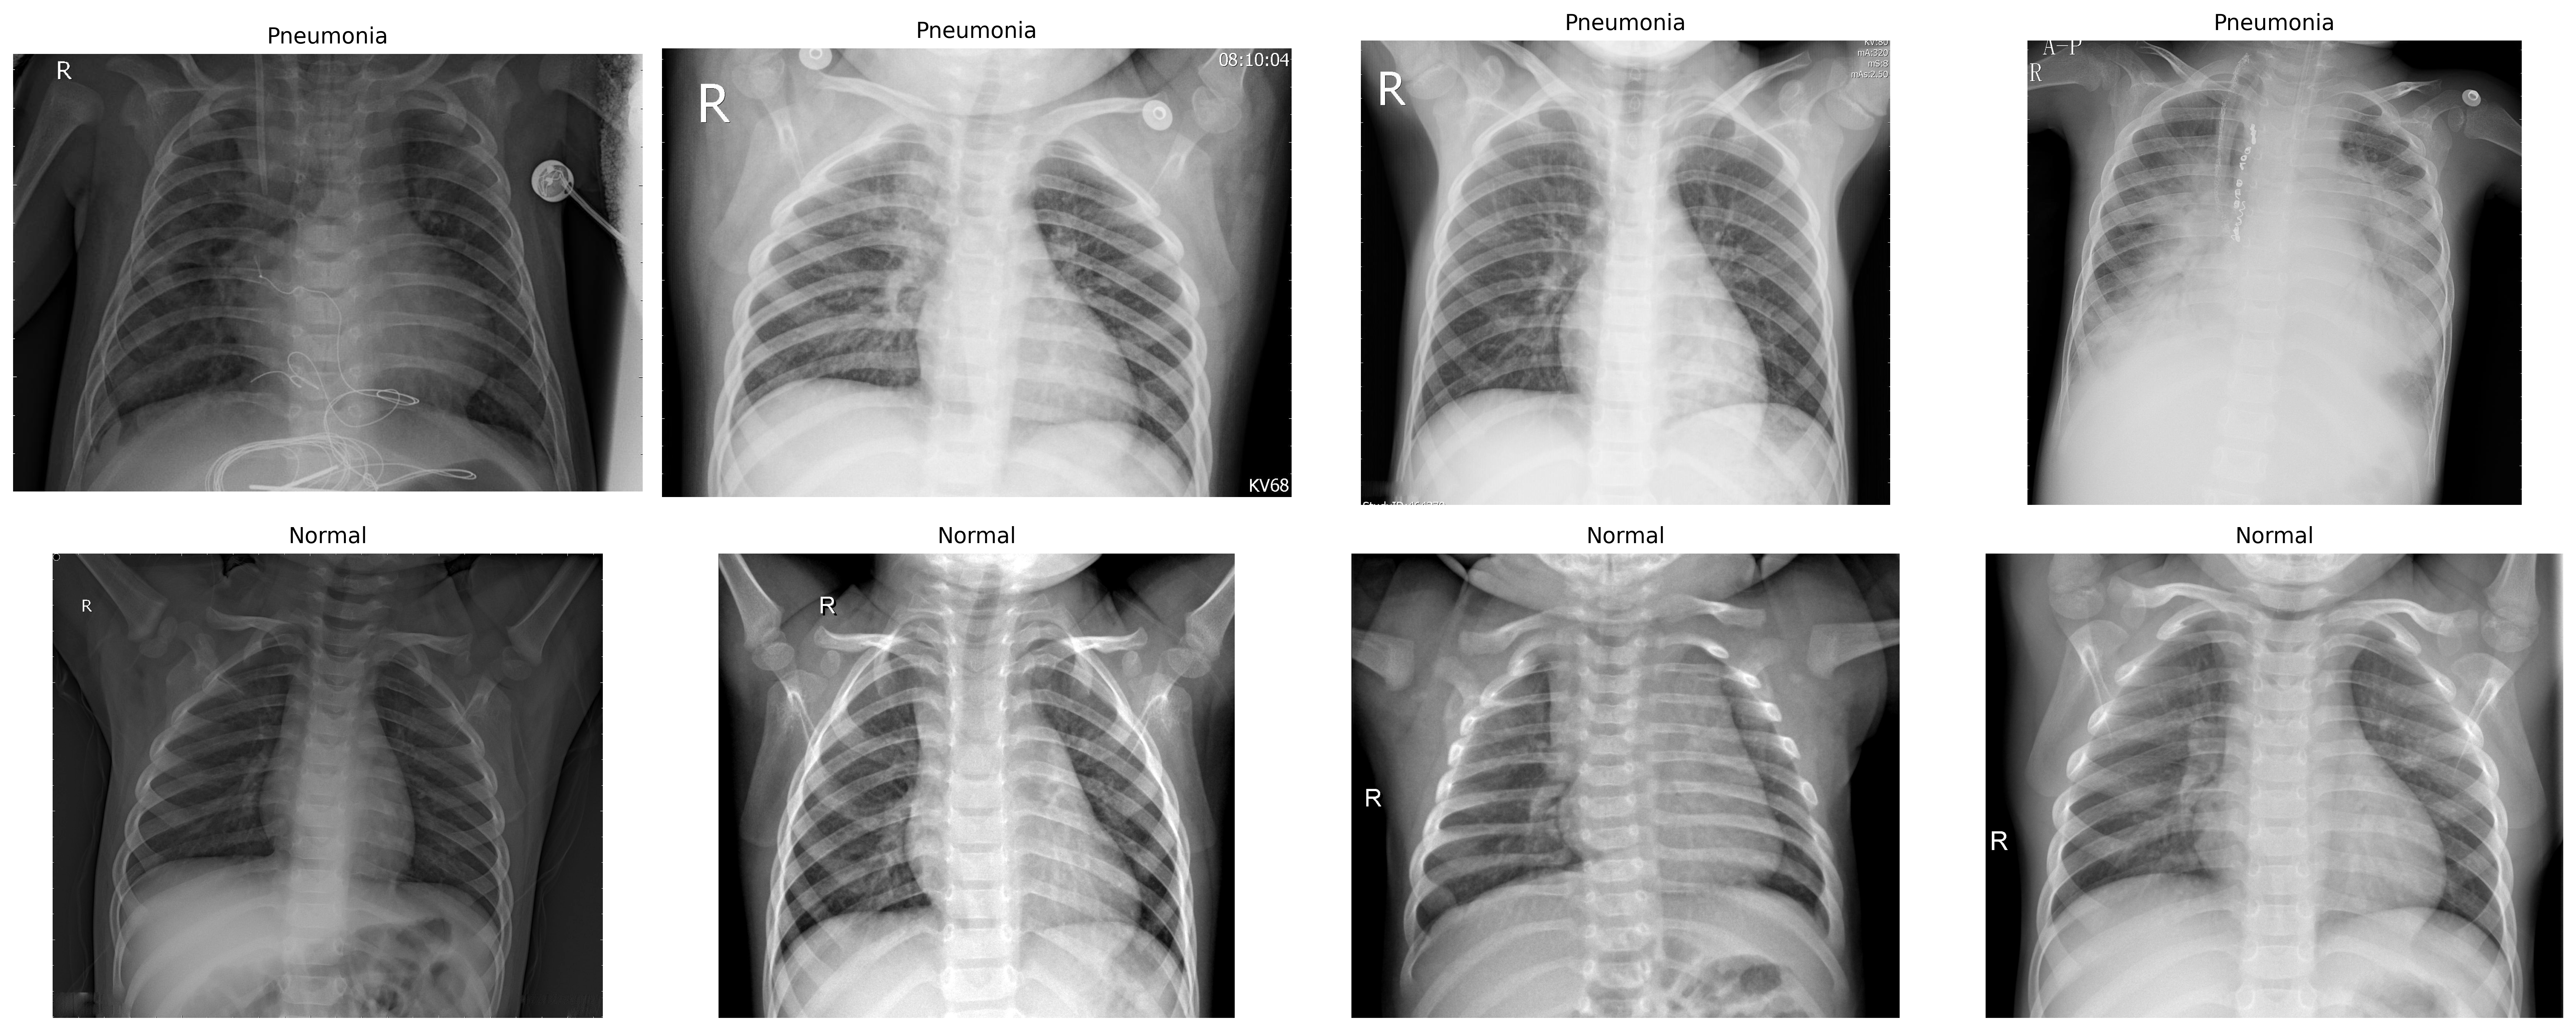

The dataset employed in this work was introduced by Kermany et al. in 2018 [20], which is publicly accessible on Kaggle. The dataset is divided into three folders - train (5216 images), test (624 images) and val (16 images), each having two subfolders - Normal (1583 images) and Pneumonia (4280 images). A total of 5,856 Chest X-ray (JPEG) images were included in the dataset.

Figure 2: Chest X-Ray Image Sample